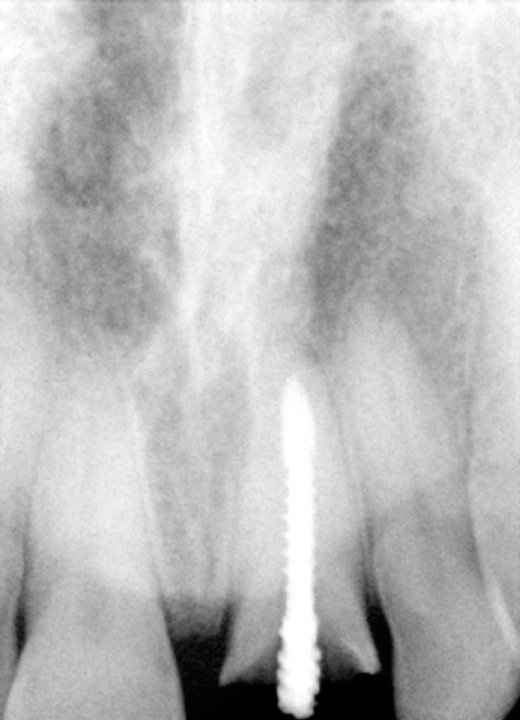

Pre-op X-Ray Showing The Fracture

X-Ray Showing The Custom Abutment In Place

Final X-Ray Showing Implant